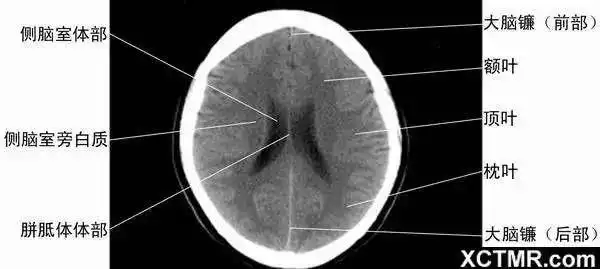

学习这些颅脑ct图,大脑运动起来升升温吧!